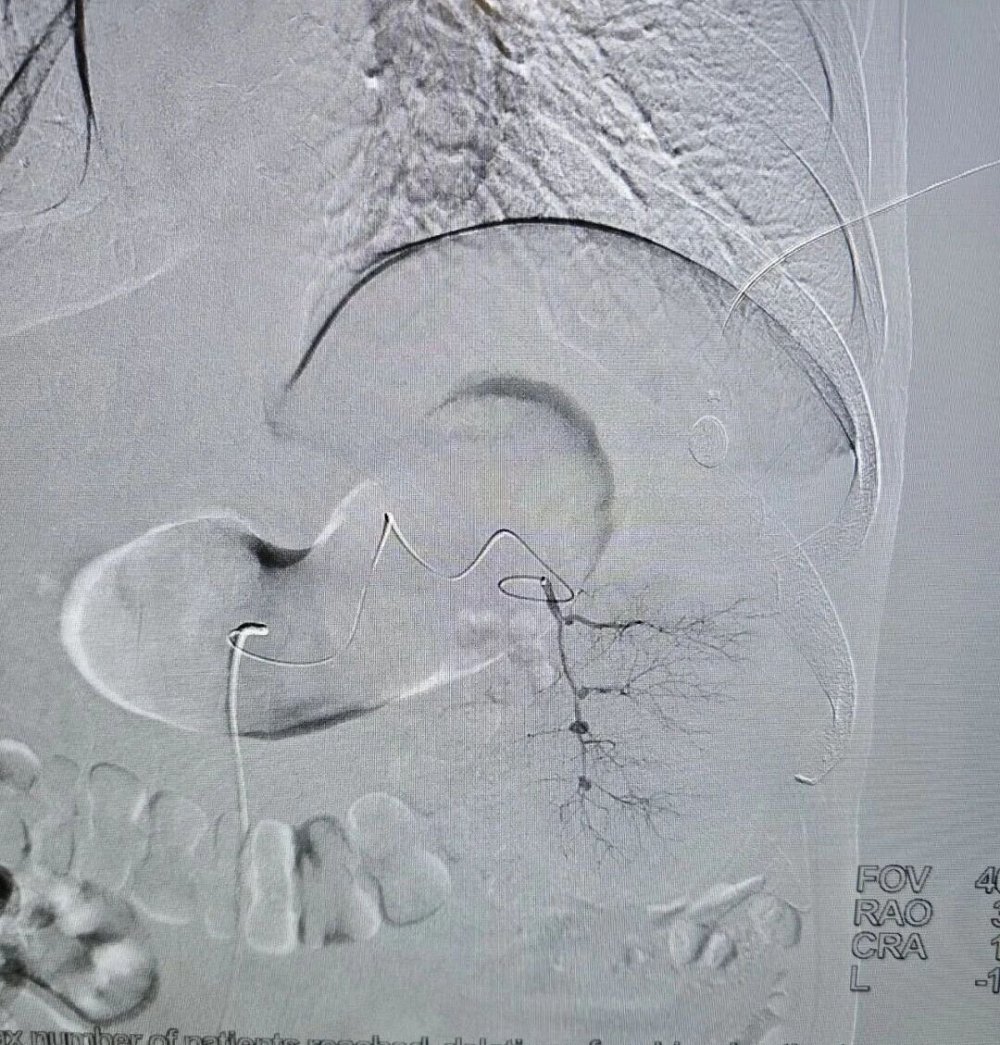

手术全程在数字减影血管造影(DSA)高清影像实时监控下开展,全程可视化操作,精准、安全、可控。

术中,介入医学科负责人卜高峰通过微细导管沿血管通路精准送达脾动脉主干,精准定位异常增生、过度亢进的病变脾组织血管分支,注入专用栓塞颗粒,选择性阻断脾脏病变区域血供,让亢进的脾组织逐步缺血萎缩,从根源解决脾功能亢进问题。

手术中,导管精准抵达脾动脉位置,清晰显示脾脏血管供血形态,为后续栓塞操作提供精准定位

栓塞过程中,通过导管向病变脾组织血管注入栓塞颗粒,精准阻断异常供血,最大程度保留正常脾组织。